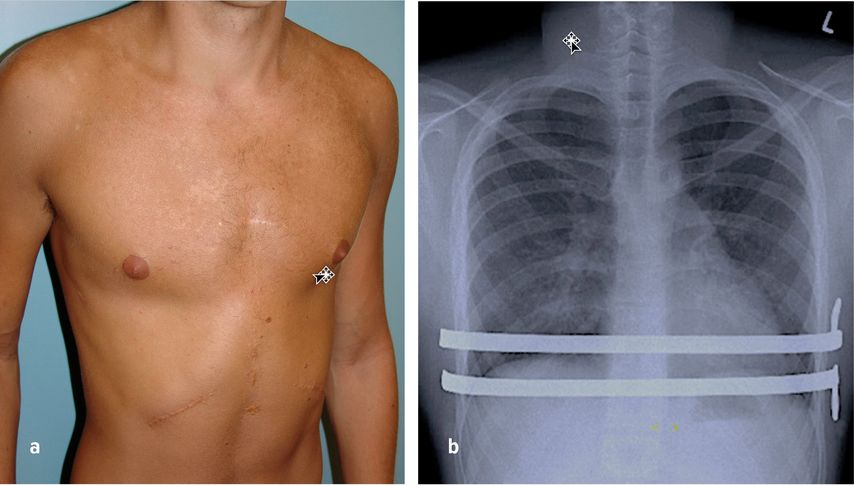

Bei Erwachsenen und bei steiferem Thorax muss, so wie auch bei deutlichen Verwachsungen im vorderen Mediastinum, die herkömmliche einfache minimalinvasive Trichterbrustkorrektur durch zusätzliche operative Maßnahmen, additiv zu den eingepflanzten Implantaten, erweitert werden.1,18 Sie beinhalten die thorakoskopische partielle Schlitzung des Perichondriums betroffener Rippen, die gerade oder schräge partielle Sternumosteotomie (z.B. zum Ausgleich der Krümmung bzw. der Rotation), ggf. Rippenknorpelresektionen (Stichwort: vorgewölbte Rippenbögen) und ggf. eine anterior-mediastinale Dissektion (Mediastinotomie) im vorderen Mediastinum zwischen Sternum und Herzbeutel (Abb.7a+b). Letztere Maßnahme erfordert einen zusätzlichen medianen subxiphoidalen Zugang zum Mediastinum.

Abb. 7: a) Postoperatives Resultat nach erweiterter Trichterbrustkorrektur, b) ap. Röntgenbild, wo zwei PSI®-Stützplatten zur Korrektur der Trichterbrust verwendet wurden. Die integrierten Stabilisator-Flügel liegen links angepasst am Thorax